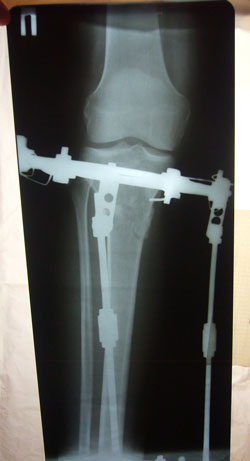

Дата операции 01.11.2012г.

Дата снятия аппаратов 22.01.2013г.

Срок лечения 80 дней.